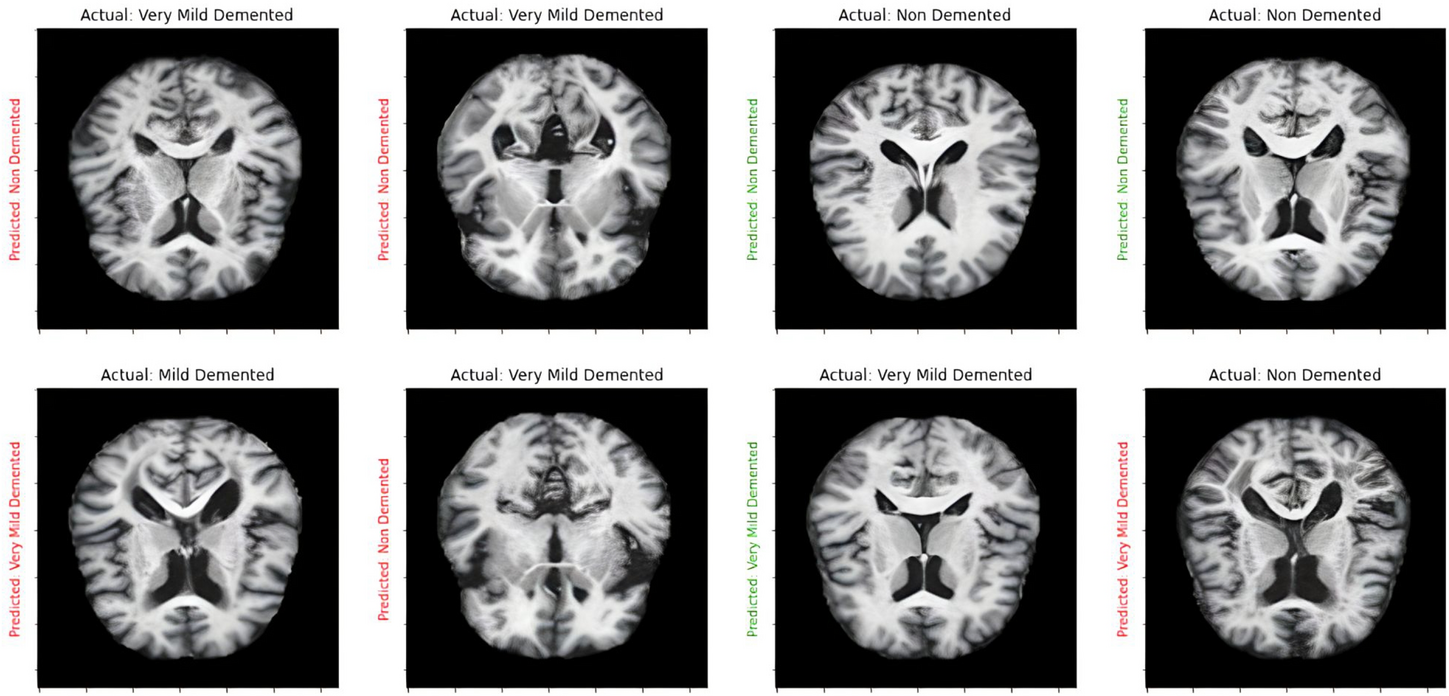

Prediction result for ensembled model.